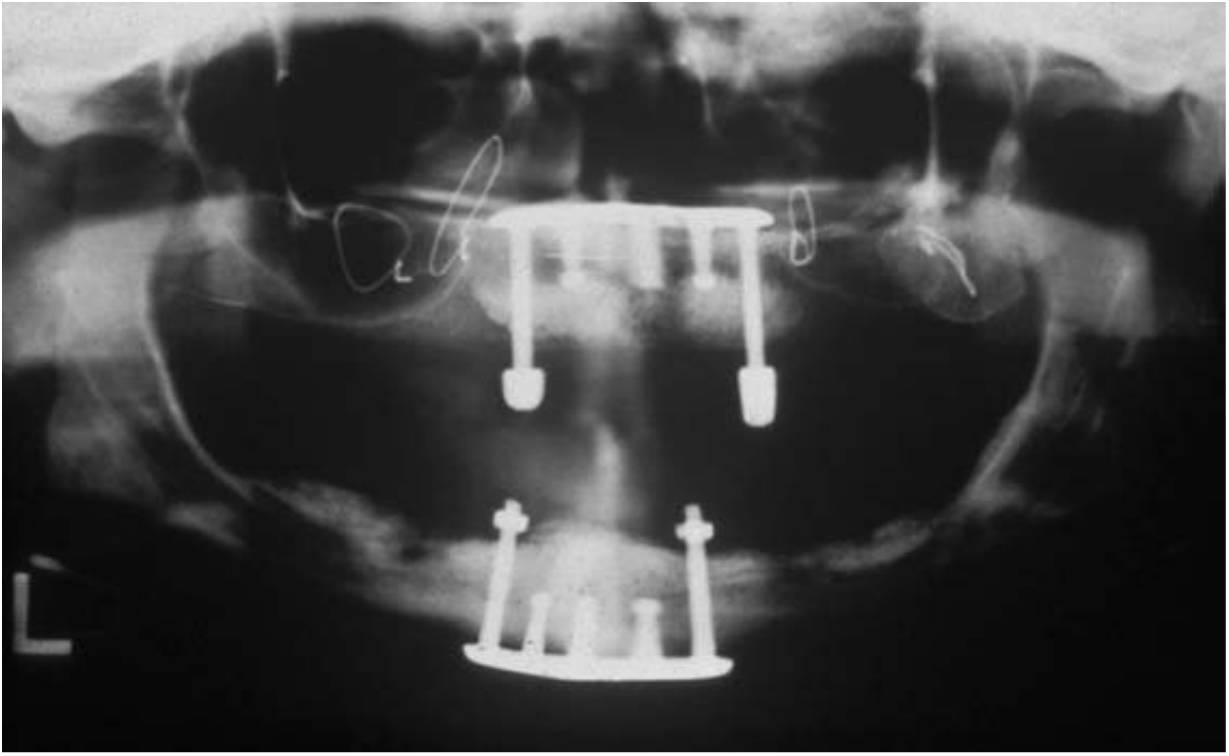

Una alternativa a la prótesis tradicional fija de metal porcelana es la restauración híbrida (v. tabla 5-2). Este di seño utiliza una estructura metálica menor, con dientes artificiales y acrílico para unir estos elementos (fig. 5-15).

Esta restauración es menos cara de fabricar y es muy estética debido a los dientes artificiales prefabricados y al reemplazo de los tejidos blandos por el acrílico rosa. Además, el acrílico interpuesto entre los dientes y el armazón puede reducir fuerza de impacto de las cargas odusales dinámicas. La prótesis híbrida es más fácil de reparar ante una fractura, y el diente artificial puede sustituirse con un riesgo menor que el añadido de porcelana a una restauración tradicional ceramometálica. En cualquier caso, la fatiga del acrílico es mayor que en las prótesis tradicionales; de ahí que la reparación de la restauración se necesite con más frecuencia.

La determinación del espacio vertical de la corona de una restauración híbrida frente a una restauración tradicional de metal-porcelana es de 15 mm desde el hueso hasta el plano oclusal. Cuando la dimensión de la que se dispone es inferior a esta, se sugiere emplear una restauración de metal-porcelana. Cuando existe un espacio vertical de la corona mayor, se suele fabricar una restauración híbrida.